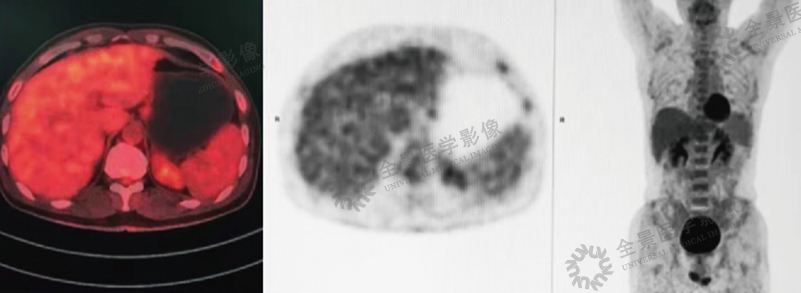

案例:青年男性,因发热伴脾肿大1个月,2016年1月来本中心行PET/CT检查,发现脾脏明显肿大、肝门区淋巴结肿大及全身骨髓腔广泛摄取,

均伴FDG明显高摄取。

结论:诊断为淋巴瘤。后临床确诊为弥漫大B细胞性淋巴瘤。

治疗前:

治疗后: